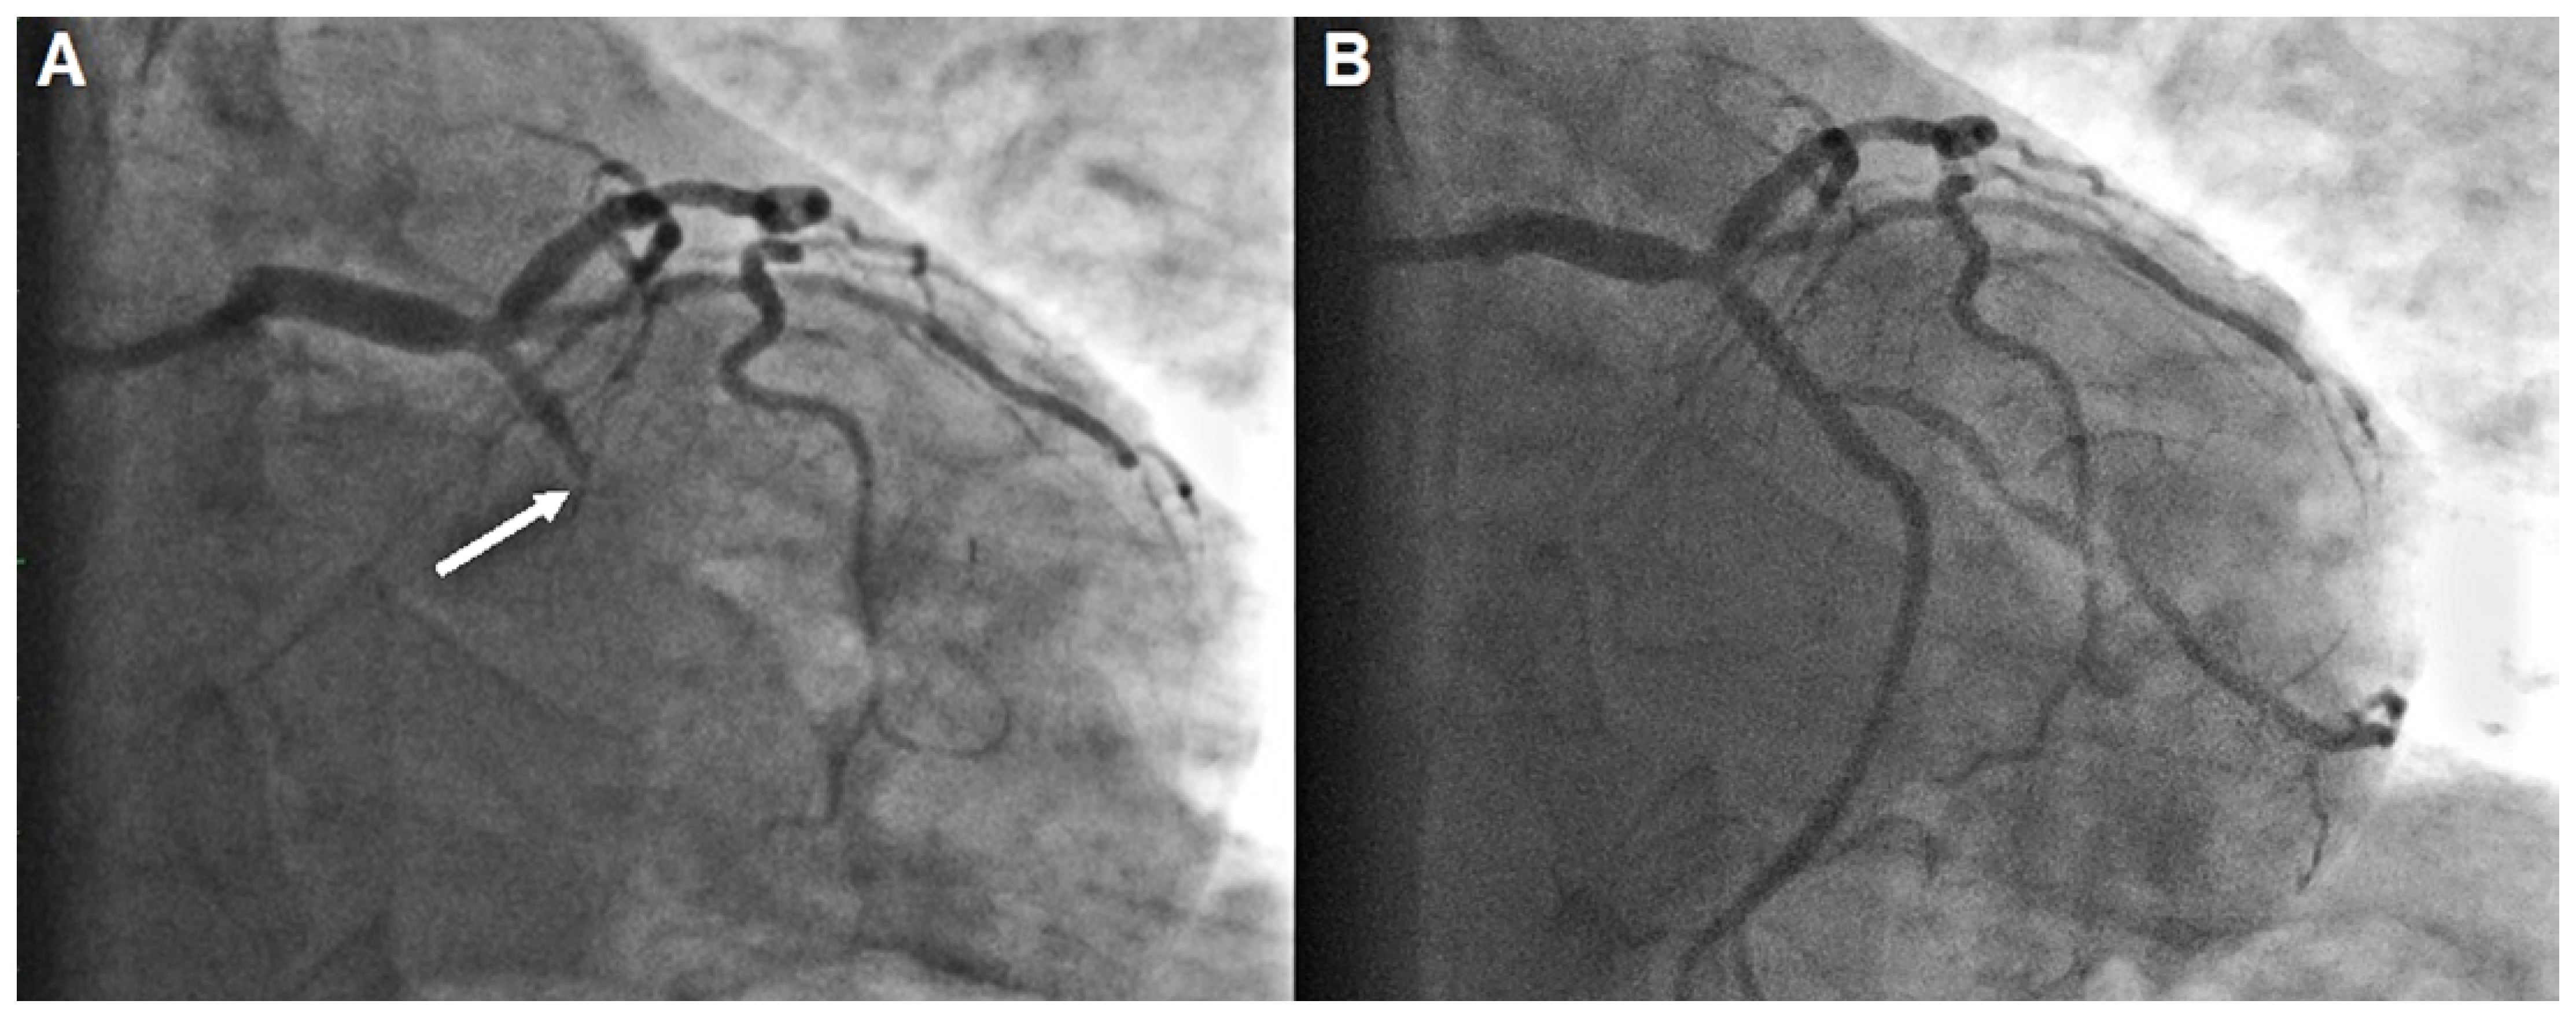

A Case of Acute Coronary Syndrome Featuring a Forgotten and Disguised Intruder

Case Presentation